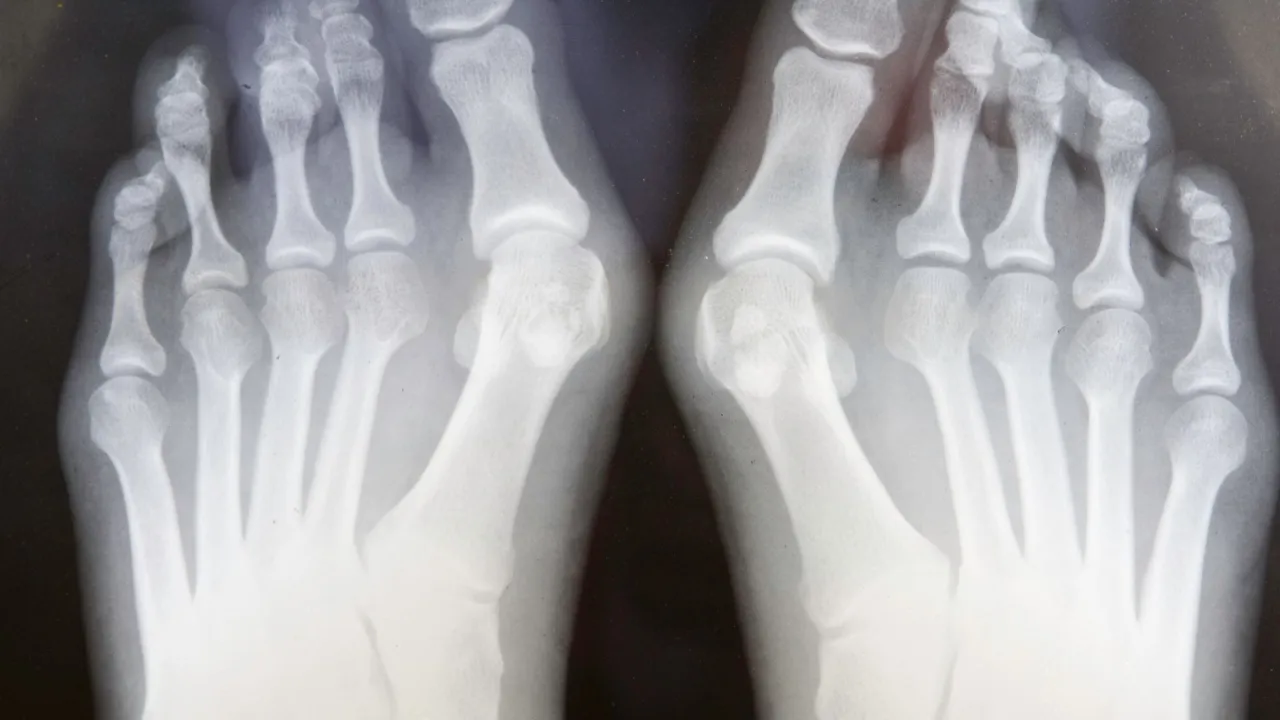

- Diagnostyka opiera się na badaniu fizykalnym oraz zdjęciu RTG stopy wykonanym w obciążeniu.

W diagnostyce haluksów nie ma nic ważniejszego niż odpowiednie badanie obrazowe. Owszem, badanie fizykalne jest podstawą, ale to zdjęcie RTG stopy wykonane w obciążeniu (na stojąco) dostarcza ortopedzie kluczowych informacji, których nie da się uzyskać w inny sposób. Dlaczego to takie ważne?

Kiedy stoisz, Twoja stopa jest obciążona masą ciała, co powoduje, że deformacje, takie jak haluksy, są znacznie bardziej widoczne i odzwierciedlają rzeczywisty stan rzeczy. Zdjęcie wykonane w pozycji leżącej może nie pokazać pełnego zakresu zniekształcenia, ponieważ stopa jest odciążona. RTG na stojąco pozwala na dokładną ocenę kątów między kośćmi śródstopia i palucha, stopnia podwichnięcia stawu śródstopno-paliczkowego, a także obecności ewentualnych zmian zwyrodnieniowych. Te dane są absolutnie niezbędne do precyzyjnego zaplanowania leczenia, zwłaszcza jeśli rozważana jest operacja. Bez tego badania, wybór optymalnej metody chirurgicznej byłby obarczony znacznie większym ryzykiem błędu.